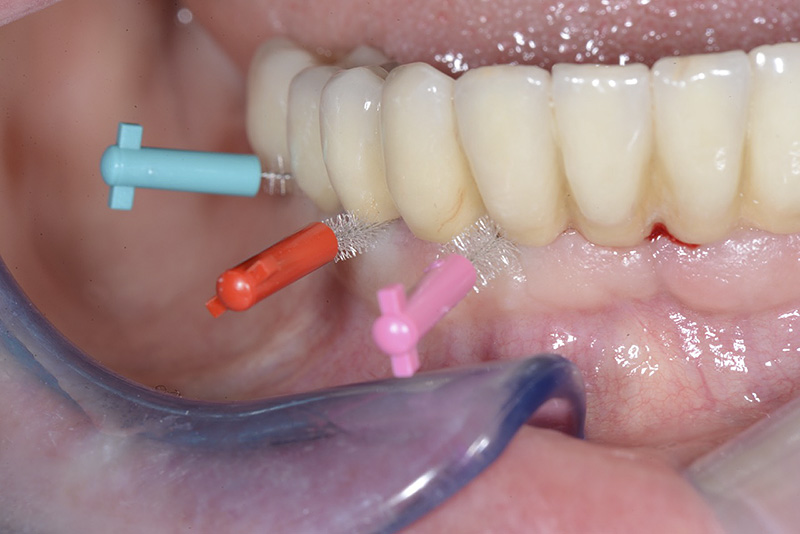

Vengono utilizzati 2 tipi di provvisori: il primo, cementato ai denti vicini, viene utilizzato dal momento dell’estrazione del dente fino ad impianto osteointegrato (circa 6 mesi); il secondo, avvitato direttamente all’impianto, ha una funzione di prova estetica ma soprattutto di guida per la maturazione dei tessuti gengivali peri-implantari portandoli verso la maturazione completa prima di posizionare la corona finale in disilicato di litio.